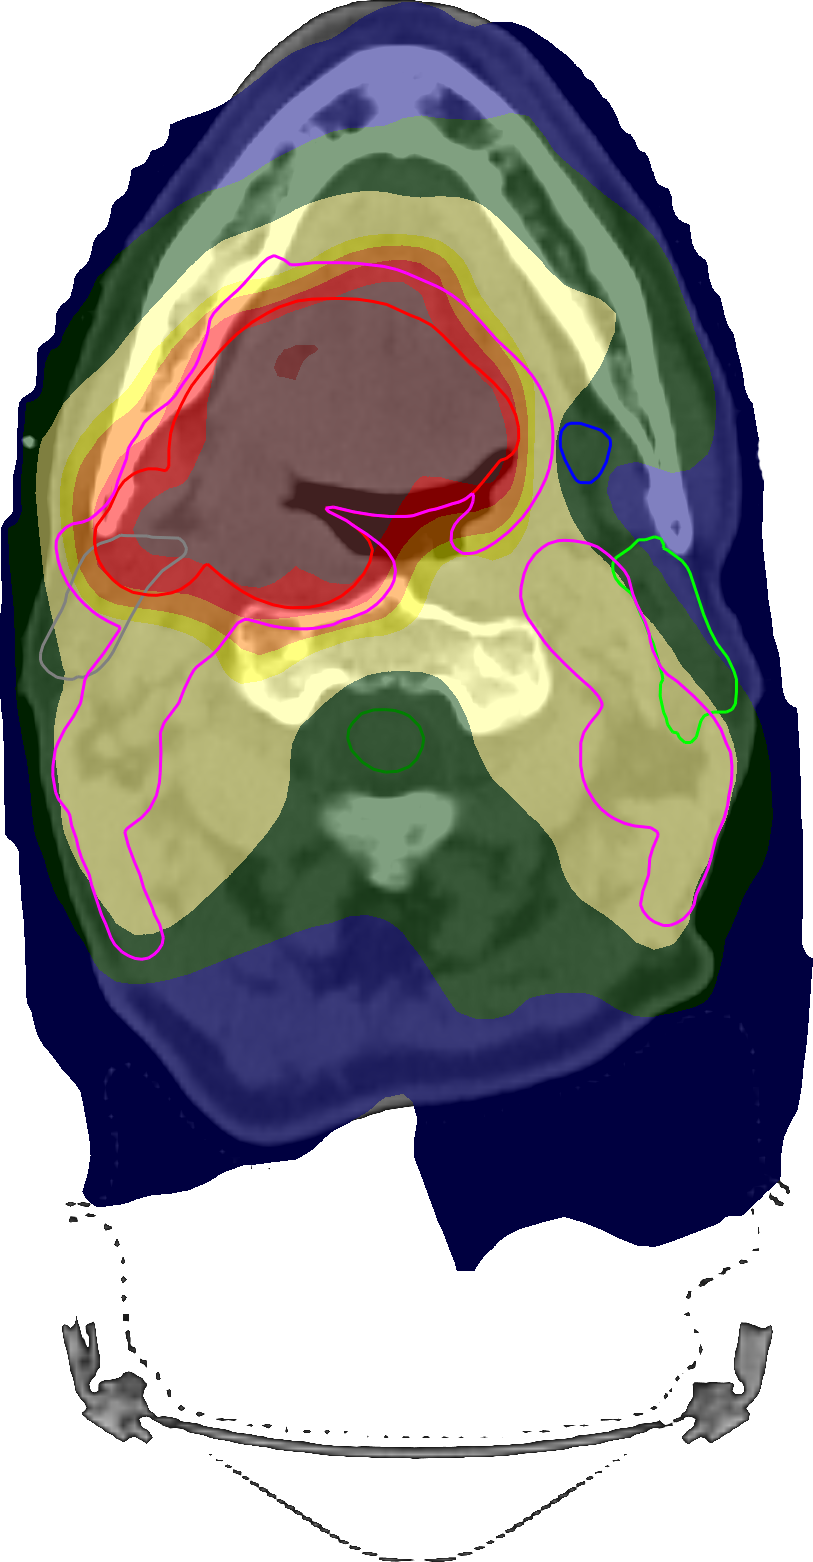

For the unconstrained formulation, Table 6 shows the particular clinical goal levels after optimization, and Figures 4(a) and 5 show, respectively, the DVHs and the spatial dose distributions. Again, we were able to fulfil all clinical goals with the direct optimization of clinical goals (using only the version including mean-tail-dose this time), whereas the conventional formulation left five clinical goals slightly unfulfilled. In particular, due to the mean-tail-dose functions, both the upper and lower tails of the targets had remarkably fewer extreme values with a D99.5%subscriptDpercent99.5\operatorname{D}_{99.5\,\%}D0.5%subscriptDpercent0.5\operatorname{D}_{0.5\,\%} range in the high-dose target of 6620cGy6620cGy6620\;\mathrm{cGy}7463cGy7463cGy7463\;\mathrm{cGy} compared to 6267cGy6267cGy6267\;\mathrm{cGy}8029cGy8029cGy8029\;\mathrm{cGy} for the conventional formulation—in fact, in a clinical setting, the latter values would likely have been unacceptable. Unnecessary dose in the external ROI was also significantly reduced, which can be seen both in DVH and in spatial dose. The fact that many goals finished within 1cGy1cGy1\;\mathrm{cGy} of their acceptance levels for the direct formulation indicates that our choice of noise level leads to an approximation error of dose-at-volume negligible for most purposes. Furthermore, the relatively poor convergence properties of conventional penalty functions can be explained by the fact that their gradients vanish when the underlying clinical goal approaches fulfilment [15], whereas this is not the case for the direct formulation. Figure 4(b) shows that smooth dose-at-volume with a ramp loss function leads to more voxels having non-negligible partial derivative than the corresponding conventional penalty function.

Refer to caption

(a)

(b)

Figure 5: Transversal cuts of the spatial dose distributions of the optimized plans obtained for the unconstrained head-and-neck test using the conventional formulation (a) and using the direct optimization of clinical goals (b).